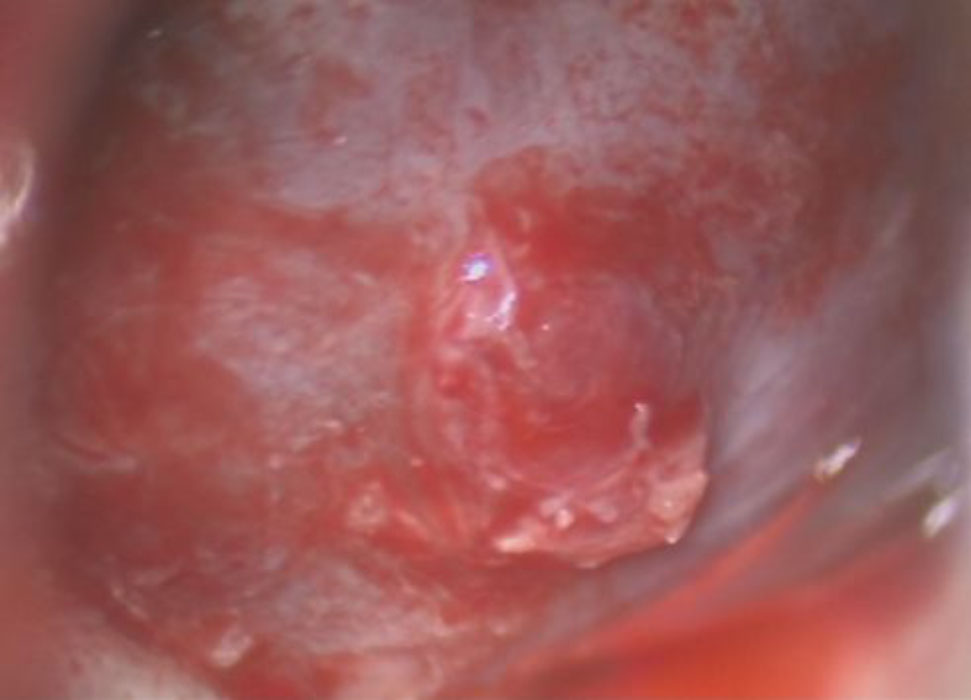

705

'25年12月

60代

下垂体腺腫

頭蓋内腫瘍摘出術

No.’25_107 手術前1

No.’25_107 手術前2

No.’25_107 摘出 前

No.’25_107  摘出 中

No.’25_107 摘出 後